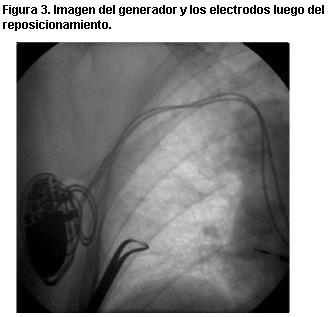

Fue reintervenida no habiéndose verificado daño de los electrodos, por lo cual se procedió al reposicionamiento de los mismos y fijación del generador al músculo pectoral mayor (figura 3), corrigiéndose la situación. La paciente se recuperó satisfactoriamente y fue dada de alta a su institución de origen.

Figura 3. Imagen del generador y los electrodos luego del reposicionamiento.